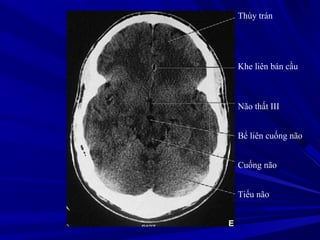

Thùy trán

Khe liên bán cầu

Não thất III

Bể liên cuống não

Cuống não

Tiểu não